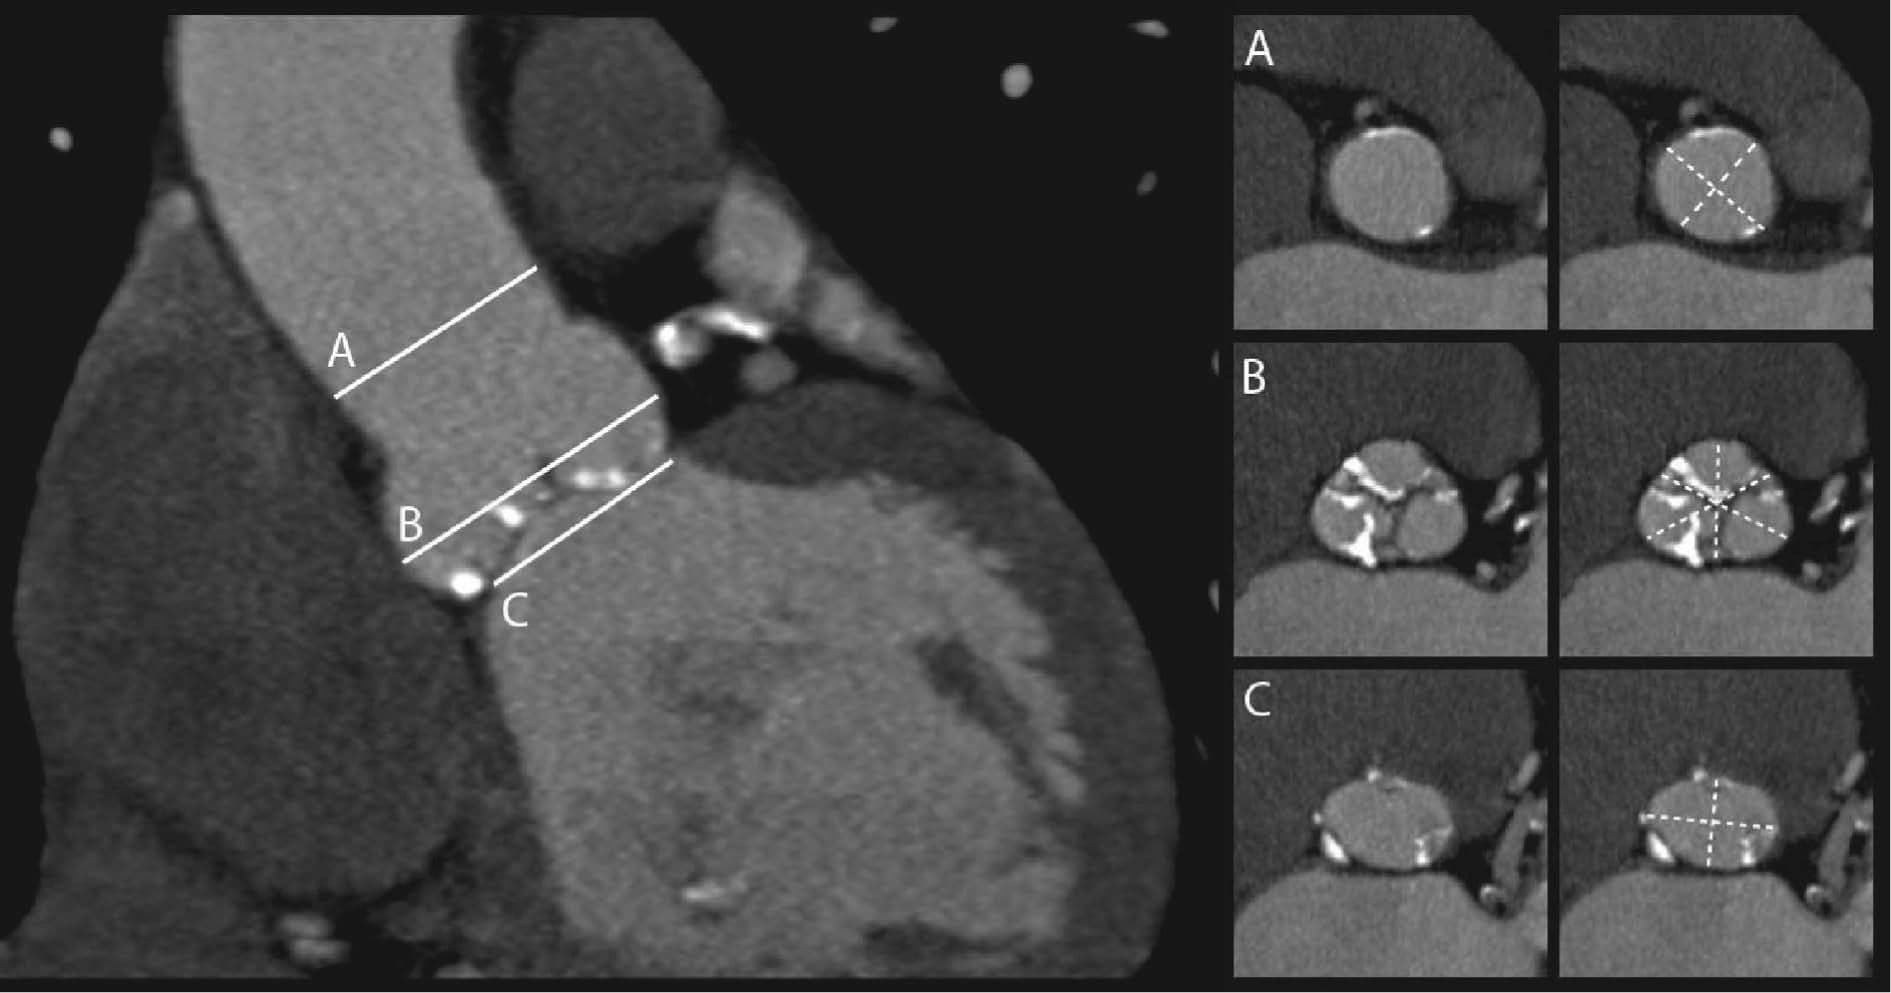

TAVI/TAVR

A TAVI (Transcatheter Aortic Valve Implantation) heart procedure, also known as TAVR, is a minimally invasive way to replace a diseased aortic heart valve using a catheter, avoiding open-heart surgery.

TAVI Procedure

Valve Replacement

Complete Analysis